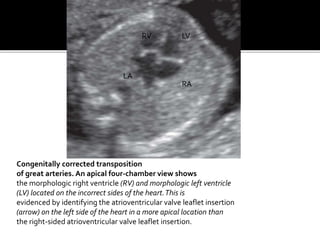

Congenitally corrected transposition

of great arteries. An apical four-chamber view shows

the morphologic right ventricle (RV) and morphologic left ventricle

(LV) located on the incorrect sides of the heart.This is

evidenced by identifying the atrioventricular valve leaflet insertion

(arrow) on the left side of the heart in a more apical location than

the right-sided atrioventricular valve leaflet insertion.

Congenitally corrected transposition ofgreat arteries. An apical four-chamber view shows the morphologic right ventricle (RV) and morphologic left ventricle (LV) located on the incorrect sides of the heart.This is evidenced by identifying the atrioventricular valve leaflet insertion (arrow) on the left side of the heart in a more apical location than the right-sided atrioventricular valve leaflet insertion. RV LV LA RA